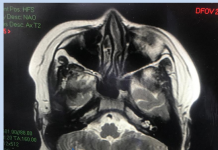

Sau tai nạn ô tô người phụ nữ Trung Quốc bất ngờ phát hiện...

(Tổ Quốc) - Một phụ nữ Trung Quốc sau khi chụp CT sau một tai nạn ô tô nhỏ đã bất ngờ phát hiện...